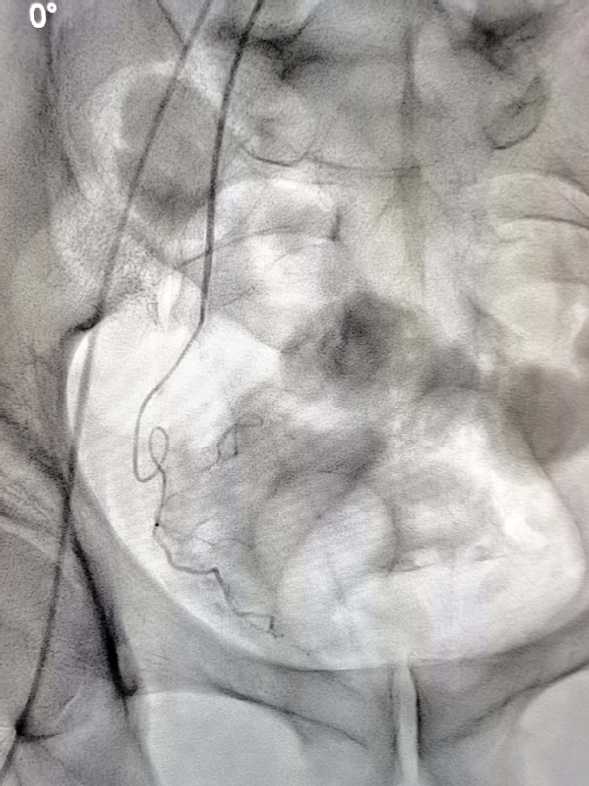

术中右侧前列腺动脉造影结果